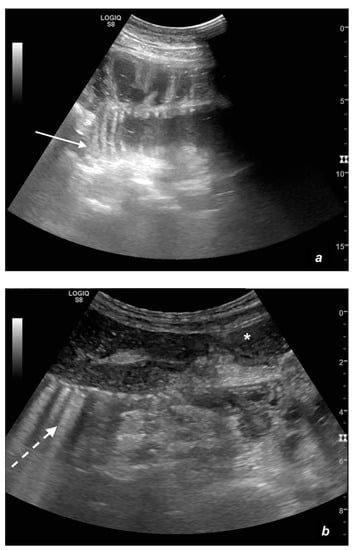

Figure 4.

A complicated SBO in a 69-year-old male with gastric cancer and peritoneal carcinosis. Ultrasound images show long (a) and axial (b) evaluations of a fluid-filled, dilated small bowel loop with hyperechogenic floating material (shown with an asterisk) (b,d). Bowel peristalsis was absent. Mild parietal and valvulae conniventes thickening are present (c,d). Downstream loops present normal caliber (bowel jump diameter). Free fluid is interposed between bowel loops (black arrow) (b).

Figure 5.

A complicated SBO presenting fluid-filled bowel loops with thickened walls with a stratified echo pattern (a) and thickened valvulae conniventes (b). Free fluid in the abdominal cavity was detected (b). Tail comet artifacts for air-fluid levels are visible (a). At the time of surgery, the bowel loop was necrotic.